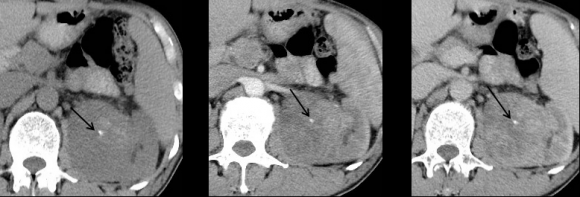

But, when we analyzed the degree of enhancement (hyperdensity, isodensity, hypodensity) in arterial (corticomedullary) and venous (nephrographic) phases showed significant difference. In arterial phase, most of clear cell RCC (21 of 39, 53.8%) showed hyperdensity, whereas none of non -ccRCC (0 of 22,0%) showed hyperdensity. The P value was 0 (P<0.05). In venous phase, ccRCC showed more hyperdensity or isodensity (9 and 4 0f 39, 23.1% and 10.3% respectively) than non-ccRCC (0 and 1 of 22, 0% and 4.5% respectively). Almost all of the non-clear cell RCC ( 21 However, we did not get any significant difference, when compared degree of enhancement in delayed phase (excretory phase). Table 3: shows the comparison of degree of enhancement in different phases in between ccRCC and non-ccRCC. The pattern of enhancement (homogeneous or heterogeneous) showed significant difference. Nonclear cell carcinoma (19 of 22, 86%) showed more heterogeneous enhancement pattern than that of clear cell carcinoma (21 of 39,53%). The P value was 0.012 (p<0.05).

Now-a-days, the incidence of renal cell carcinoma is increasing due to increasing risk factors (obesity, smoking) and utilization of modern imaging techniques [11][12][13]29]. A majority of renal tumors are incidentally diagnosed on medical imaging, that's why most of them are asymptomatic, small in size and present at an earlier stage [14,27]. It is important to discriminate clear cell RCC from non-clear cell RCC because of ccRCC is generally considered to have a worse prognosis and is treated differently than other subtypes [15][16][17][18]27]. Several study has been done previously to differentiate clear cell RCC from non-clear cell RCC by using imaging modalities. The most consistent finding was that, degree of enhancement was the most valuable parameter for differentiation of renal cell carcinoma subtypes. Clear cell RCC S enhance to a greater degree than other subtypes of malignant lesions [8,10,[19][20][21][22]. Some researchers stated that the strong enhancement of conventional renal carcinoma is caused by it , s rich vascularity and alveolar architecture at histologic examination [4,10,23]. Our study consistent with these study. In this study, we found ccRCC (53.8%) showed more hyperdensity than that of non-ccRCC(0%). Most of non-ccRCC (95.5%) had hypodensity in all phases.